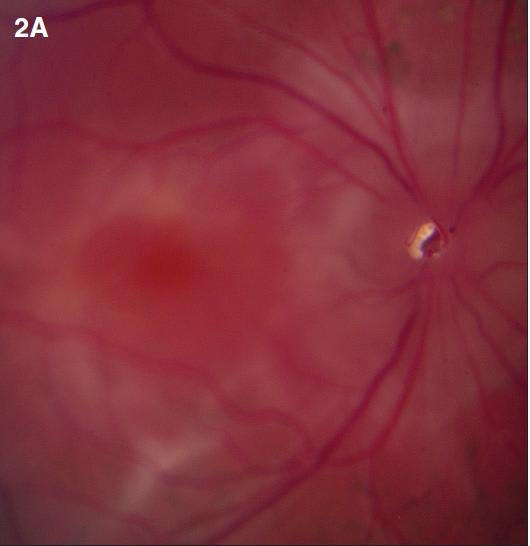

Figure 2. Diffuse choroidal hemangioma. The patient was a nine-year-old boy with history of Sturge-Weber syndrome, referred due to decreased vision (20/200) and subretinal fluid in the right eye. The fundus exam revealed retinal pigment epithelium mottling around the optic nerve with a surrounding cuff of subretinal fluid (A). B-scan ultrasonography demonstrated a solid, highly echogenic lesion, with diffuse choroidal thickening (B). OCT showed subretinal fluid with cystic spaces in the outer retinal layers (C). One year after treatment with external beam radiotherapy (20 Gy in 10 fractions, 2 Gy/fraction), the fundus exam revealed a regressed hemangioma (D). Tumor regression was confirmed by B-scan ultrasonography (E). Concomitant resolution of subretinal fluid was noted on OCT (F). Visual acuity improved to 20/60.

B-scan ultrasonography demonstrates solid, highly echogenic lesions, with diffuse choroidal thickening (Figure 2b), and high internal reflectivity on A-scan. Early hyperfluorescence with persistence of hyperfluorescence through the late phases of the angiogram are seen with fluorescein angiography. Similar findings are observed on ICG, with a characteristic lacy intrinsic vascular pattern, with a diffuse distribution.16 OCT may be used to confirm the presence of subretinal fluid (Figure 2c).